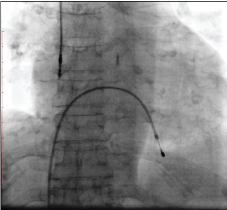

The patient was again admitted with one episode of syncope and twitching in the right upper quadrant of the abdomen. Electrocardiogram showed atrial fibrillation with a ventricular rate of 36/minute. A pulsation in her abdomen due to diaphragmatic stimulation was observed. Temporary pacemaker lead was inserted through the right femoral route and connected to the pulse generator. Fluoroscopy showed twisted ventricular lead and its retraction into the right atrium (Figure 1 and Figure 2). A diagnosis of pacemaker Twiddler's syndrome was made. Under all aseptic precautions, the pacemaker pocket was immediately reopened. The condition of the lead just after opening the pocket and after uncoiling is shown (Figure 3 and Figure 4). A new active fixation screwing ventricular lead was inserted at the right ventricular apex. The parameters were checked, R wave, the threshold, and lead impedance were 14 mV, 0.5 V, and 700 ohms, respectively. The pulse-generator was fixed on the pectoral muscle with non-absorbable suture. Postoperative hospital stay was uneventful, and the patient was asymptomatic at subsequent follow-ups..

Figure 1: Fluoroscopy showing twisted ventricular lead. View Figure 1

Figure 2: Fluoroscopy showing retracted ventricular lead into the right atrium. View Figure 2